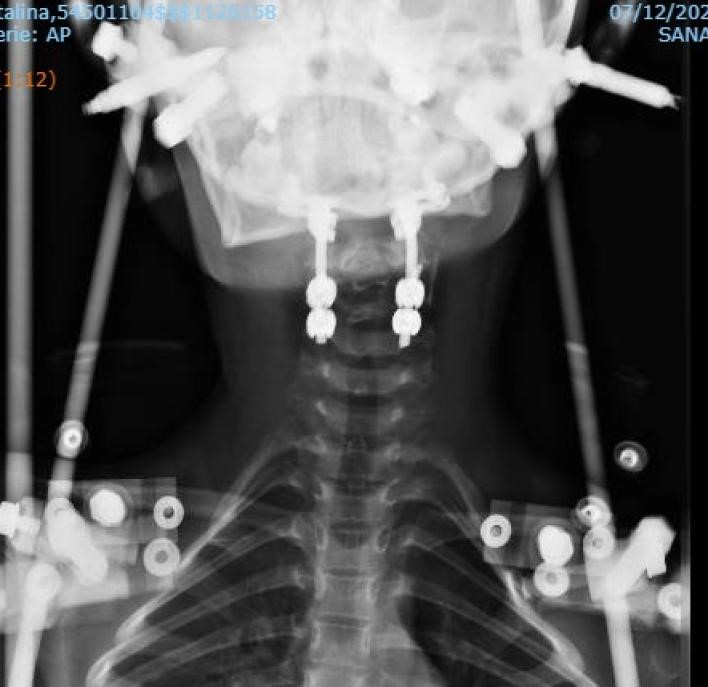

Se decide en la misma internación planificación y tratamiento quirúrgico, cirugía con monitoreo medular intraquirúrgico, previo al abordaje se coloca el halo chaleco y observa reducción con radioscopia intraquirúrgica. Por abordaje posterior se realiza artrodesis instrumentada: desde occipital a cuarta vértebra cervical con tornillos y barras bilaterales además de injerto autólogo (Figura 5).

Figura 5: Radiografía cervical postoperatoria